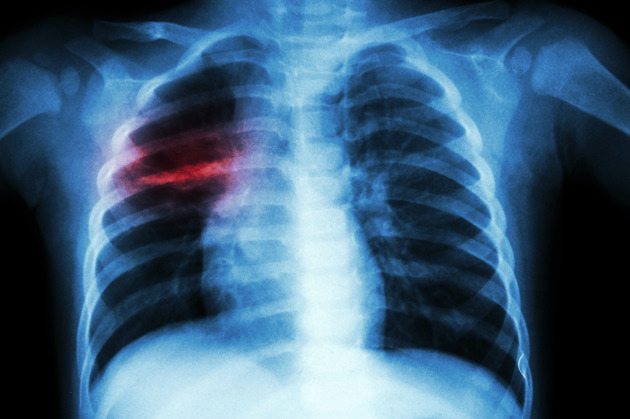

Tuberculose tem cura. A doença infecciosa afeta prioritariamente os pulmões e pode ser transmitida se o paciente não entrar em tratamento ou não realizá-lo de forma adequada. O principal sintoma da doença é a tosse persistente por mais de três semanas, com ou sem catarro. Qualquer pessoa com esse quadro deve procurar uma unidade de saúde para fazer o diagnóstico. A Organização Mundial da Saúde (OMS) estima que, atualmente, existam nove milhões de casos novos da doença no mundo.

Pacientes com suspeita de tuberculose já contam com o teste rápido, que detecta a presença do bacilo causador da doença em duas horas e identifica se há resistência ao antibiótico rifampicina, usado no tratamento. O recurso está disponível em 94 municípios, englobando todos os estados e o Distrito Federal. Os testes foram distribuídos em cidades estratégicas para o controle da tuberculose, onde se concentram 60% dos casos novos do país, o que engloba todas as capitais e os municípios com mais de 130 casos novos de tuberculose. As capitais Porto Alegre, Cuiabá, Recife e Manaus são as mais acometidas pela doença, com mais de 90 casos por 100 mil habitantes. Ao todo, o Ministério da Saúde distribuiu 160 máquinas, com capacidade de realizar, juntas, 640 mil testes por ano.